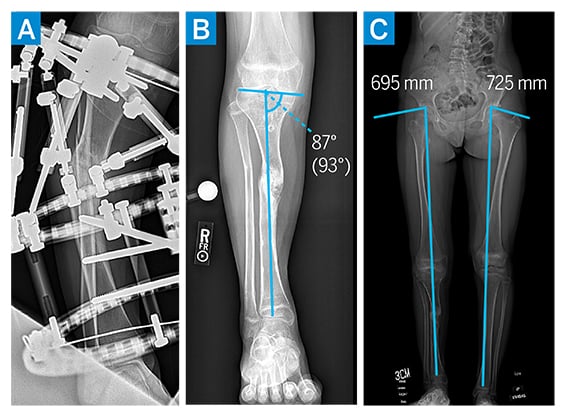

Initial radiographs demonstrated a 34° varus deformity of the right proximal tibia secondary to a hypertrophic nonunion (Fig. 1A–C), as well as a proximal tibial recurvatum deformity secondary to premature asymmetric closure of the proximal tibial growth plate. Full length standing radiographs demonstrated a roughly 4-cm leg length discrepancy. Computed tomography (CT) and magnetic resonance (MR) imaging of the right tibia confirmed fibrous nonunion of the proximal tibia, without radiographic evidence of ongoing infection. Laboratory values were within normal limits.

Figure 1

Figure 1: (a–c) Preoperative imaging demonstrating varus and recurvatum deformity of the right proximal tibia diaphysis with associated limb leg length discrepancy.